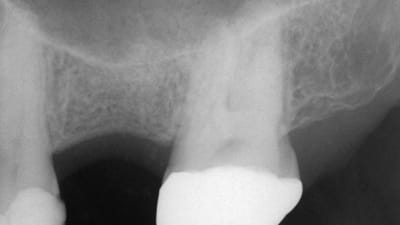

Case Series Implantology Oral Surgery Simultaneous Crestal Sinus Elevation and Implant Placement Using a Ribose Cross-Linked, Collagen Bone Graft Material: Case Series of 28 Consecutive Patients By Sergio Rubinstein, DDS March 01, 2020 16 min read